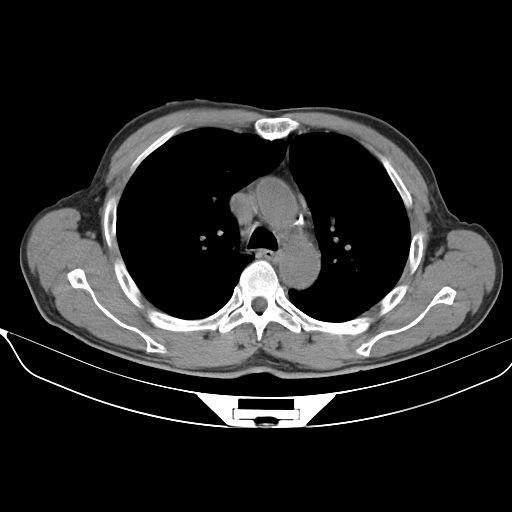

以下是引用心路寻觅在2010-3-1 10:23:00的发言:[br]1、考虑左肺上叶周围型肺癌[br]2、右上肺陈旧性病灶。[br][br][本贴已被 心路寻觅 于 2010-3-1 10:40:18 修改过]

以下是引用shuiyuan在2010-3-1 10:45:00的发言:[br]考虑左肺上叶中心型肺癌伴阻塞型炎症,邻近胸膜受侵。